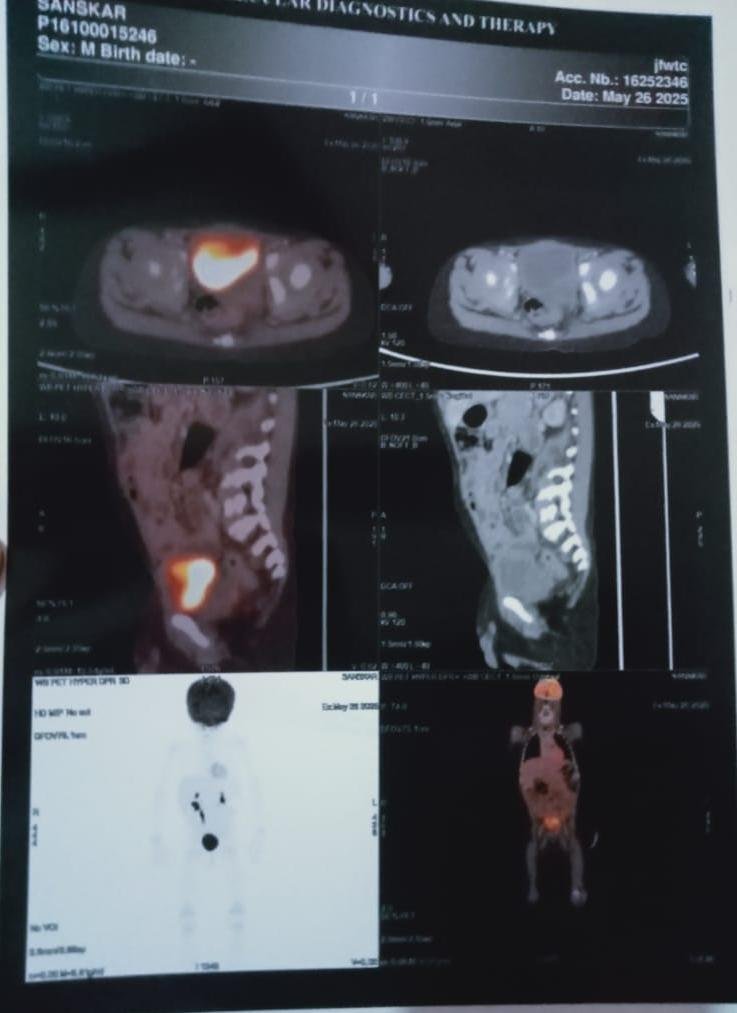

Help 3-Year-Old Sanskar Fight Cancer